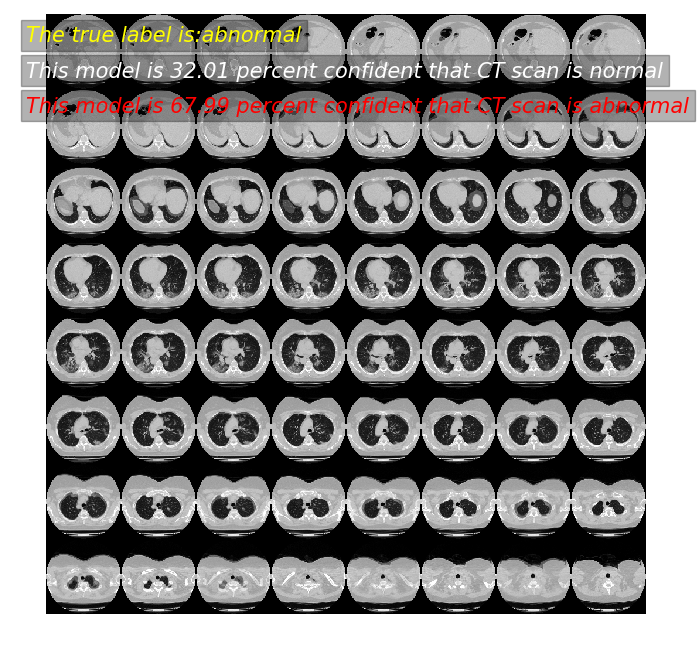

predictor(2)

模型预测: 43.85 概率,这张CT normal

模型预测: 56.15 概率,这张CT abnormal

真实标签为: abnormal

predictor(11)

模型预测: 32.01 概率,这张CT normal

模型预测: 67.99 概率,这张CT abnormal